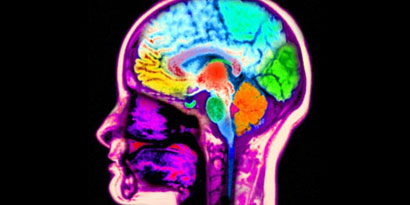

Cérebro de psicopatas tem deformação que evita medo ou culpa

Analisando tomografias computadorizadas de cerca de 40 prisioneiros, os pesquisadores chegaram à conclusão de que o cérebro dos condenados não têm certas ligações em áreas responsáveis por sentimentos como medo ou culpa.

De acordo com o professor Michael Koenigs, autor do estudo, esse é o primeiro trabalho que mostra claramente diferenças funcionais na estrutura do cérebro de indivíduos diagnosticados com psicopatia. Com isso, ao menos em tese, é possível prevenir comportamentos do gênero caso os pacientes sejam diagnosticados com antecedência.